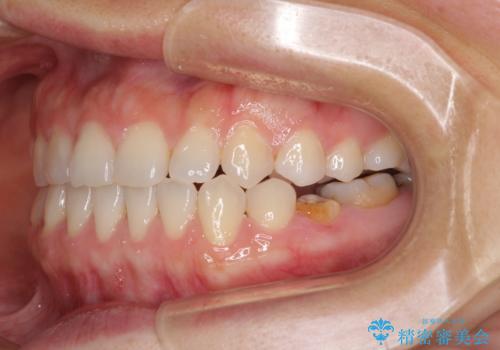

- 上下の前歯の隙間を気にして来院された患者様です。

インビザラインを用い、上下歯列のスペースを閉じていくこととしました。

治療期間中は奥歯がほとんど咬めない状態が続き、食事に大変苦労されました。

最終的には隙間もしっかりと閉じ、奥歯も咬みやすい状態でしあげることができました。